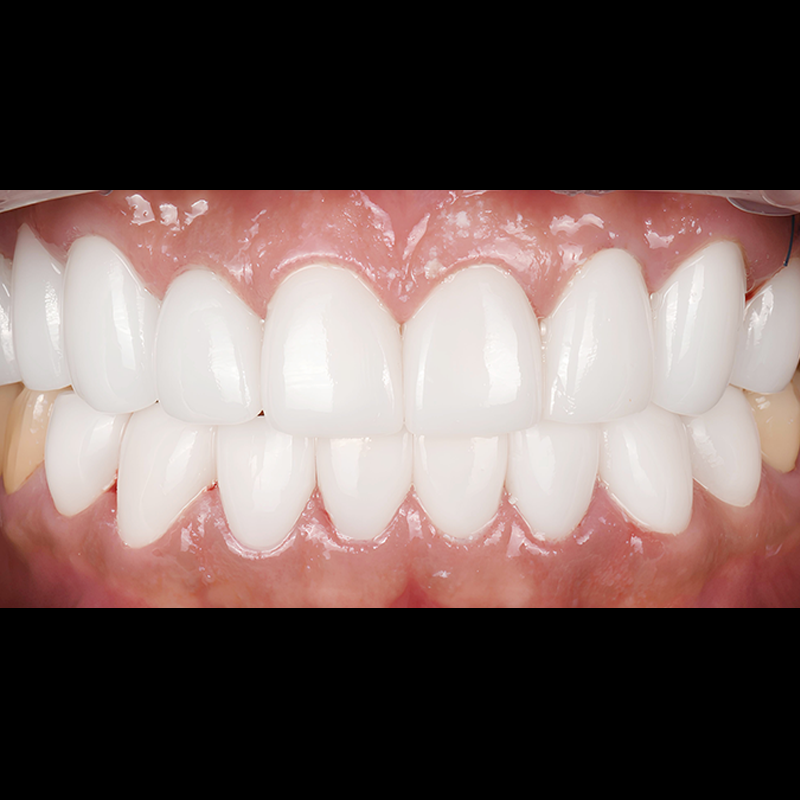

BEFORE AFTER

ルシネート前後の写真 2025.04.18

歯の着色治療のため、最小削除/無削除のルシネートを付着し、なめらかで自然な歯に仕上げました。